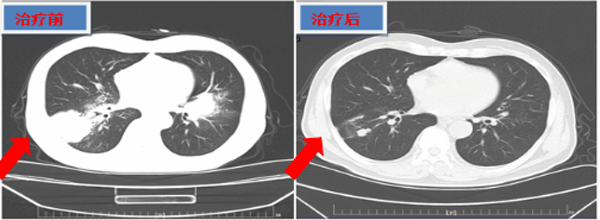

治疗后,患者咳嗽、咳痰及右髋部疼痛明显减轻,生活质量明显提高,同时复查CT提示肿瘤明显缩小。二一五医院肿瘤内科医护的专业治疗与悉心关爱让患者及家属深受感动,亲自送来锦旗和感谢信,肿瘤内科团队通过合理治疗带给了患者更长的生存期,让患者及家属满眼绝望的住院,充满希望的出院。